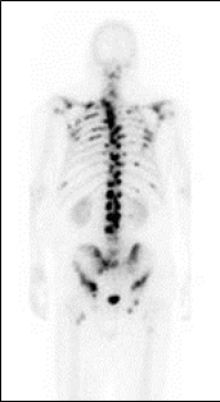

El sistema esquelético es el principal sitio de metástasis en pacientes con cáncer de próstata, adonde llega por vía sanguínea. La comunicación se refiere a un estudio de fase III para el tratamiento con radioisótopos usando cloruro de Radio-223 (223-Ra), que presenta afinidad por los sitios de metástasis ósea donde deposita partículas alfa con eficaz acción tumoricida. Las partículas alfa tienen un corto alcance de penetración, por lo cual no afectan significativamente los tejidos sanos circundantes ni la médula ósea. En principio, el agente terapéutico se está estudiando para el tratamiento de cáncer de próstata resistente a la castración, una forma en etapa tardía que se caracteriza por extensas metástasis óseas que no responden al tratamiento.

La expectativa de vida de un paciente con cáncer de próstata avanzado sometido a castración como tratamiento extremo de supresión hormonal es de unos tres a cinco años después del diagnóstico. Este estudio doble ciego y randomizado demostró que, de los 921 pacientes tratados con Ra-223 o placebo, aquellos que recibieron el fármaco vivieron un promedio de tres meses más. La terapia se administra en seis inyecciones a intervalos de cuatro semanas. Además de la prolongación de la supervivencia, en los pacientes tratados con Ra-223 también se retrasa la aparición de complicaciones debidas a las metástasis óseas. El monitoreo de la terapia es posible gracias a las técnicas de imagen molecular (gammagrafía y tomografía por emisión de positrones).